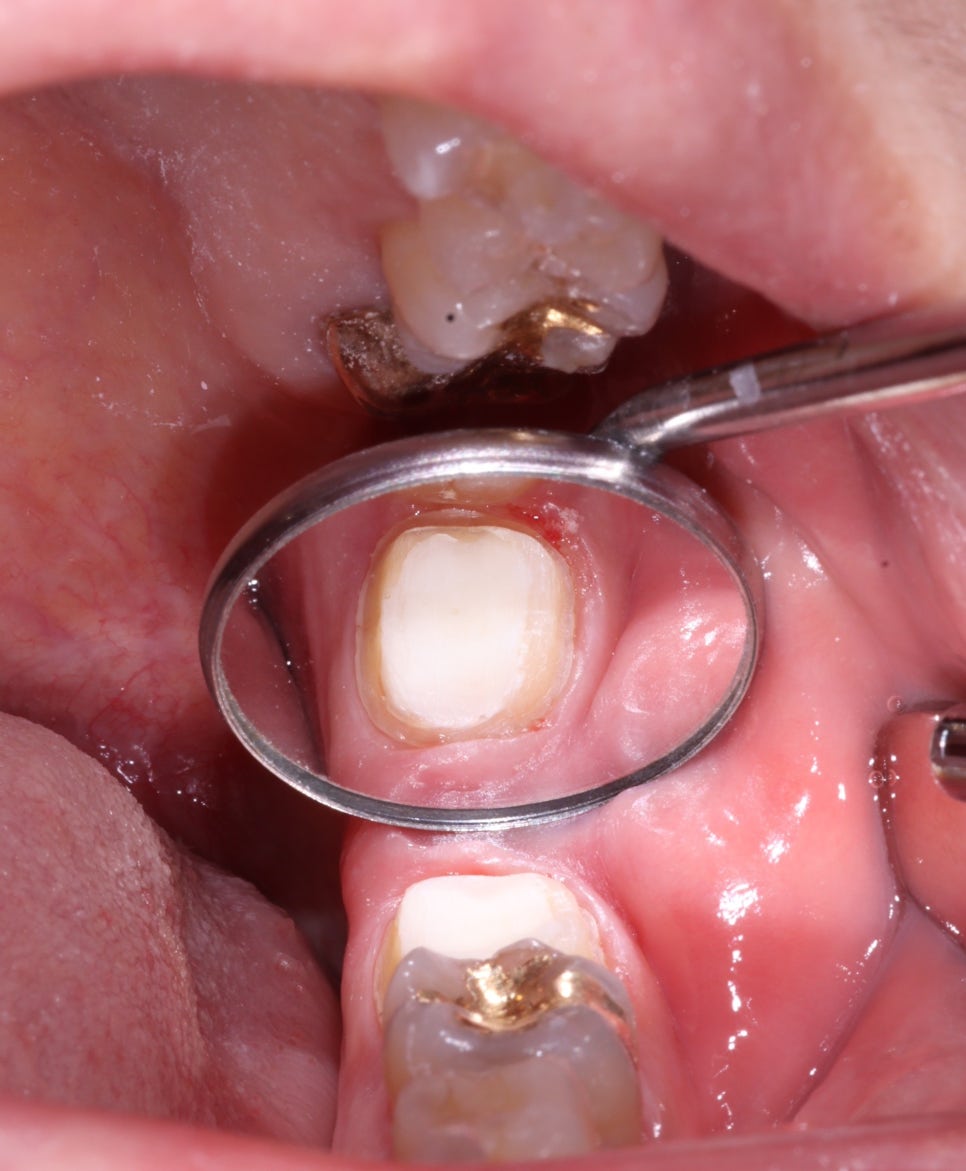

치아 내부에는 '코어'라고 부르는

레진을 강력하게 접착해서

신경치료한 치아를 보강했습니다.

그리고 크라운을 씌울 수 있는 형태로

치아를 다듬었고요.

골드인레이를 제거하고, MTA를 깔고

코어를 메꾸고, 프렙하고..